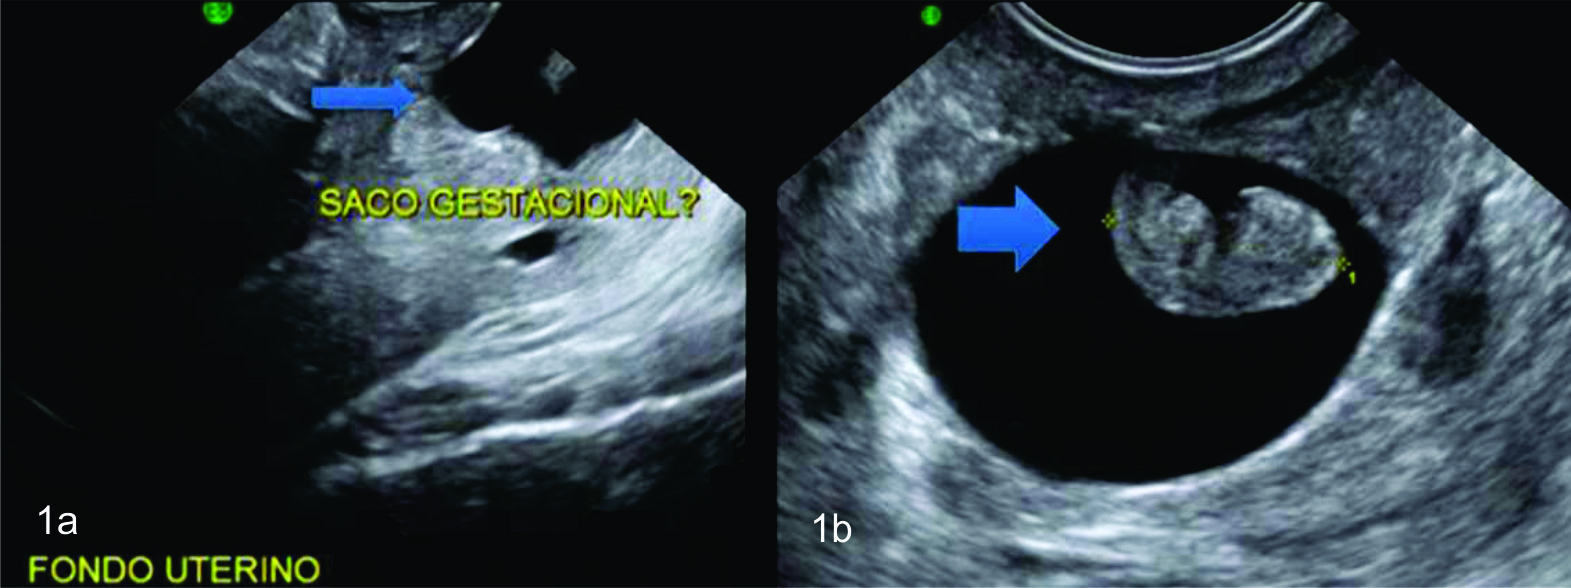

Se han propuesto 2 criterios imagenológicos adicionales para distinguir embarazo ectópico cervical, de un aborto cervical. (5) El “signo de deslizamiento”; se detecta en ecografía tranvaginal cuando se aplica una suave presión en el cuello uterino con el transductor, el saco gestacional de un aborto se desliza contra el canal endocervical; este movimiento de deslizamiento no será encontrado en un embarazo cervical implantado. El segundo criterio es la demostración de flujo peritrofoblastico con Doppler; el saco no viable transitoriamente pasando a través del cuello uterino no tendrá flujo peritrofoblástico, ya que es separado de su aporte vascular.

Figura 4

Punción ecoguiada

Se observa aguja (flecha) con extremo en el interior del saco gestacional. La imagen corresponde a saco gestacional de localización cervical, donde se constata orificio cervical interno y externo cerrados.